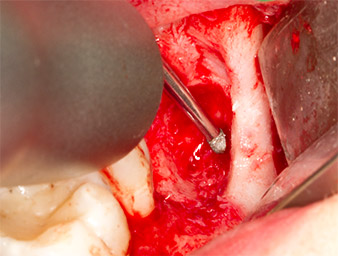

To obtain autogenous material for subsequent wound treatment, healthy bone chips were harvested from the surroundings of the root remnant with a piezo surgical instrument (Piezomed B5) (Fig. 5).

The autogenous tissue was removed with the scraper-shaped section of the working part of the instrument and stored in a physiological saline solution until further use (cf. Fig. 13).